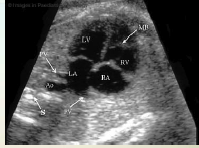

On transverse 4 chamber heart note the heart

Size: 1/3rd the size of the thorax

Axis: Between 40-45 degrees from the midline

*Should NOT be greater than 45 degrees

Position in thorax: Ventricles pointing toward the left

Surrounding fetal anatomy

heart anatomy

Both ventricles

Interventricular septum

Both atria

Atrial septum

Foramen ovale

Papillary muscles

Great vessels

Pulmonary artery

Aorta

Atrioventricular valves

Make sure they both open during diastole & close during systole (Right side is Tricuspid valve, Left side is Mitral valve)

Left atrium lies closest to the fetal spine

Four chambers should be nearly equal in size

Right ventricular apex may appear thicker due to the presence of the moderator band

Foramen ovale flap into left atrium